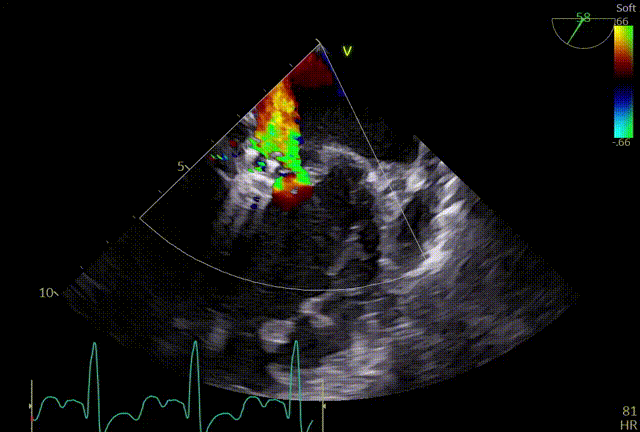

术前TEE及左房压

1区

1区带彩

2区

2区带彩

3区

3区带彩

3D

3D带彩

术前肺静脉频谱

3区gap

术前左房压